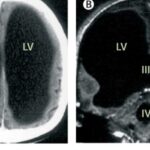

A remarkable medical case from France has forced scientists to rethink one of the biggest questions in neuroscience: what does it really take to be conscious? First documented in the medical journal The Lancet in 2007, the case involved a middle-aged man whose brain scans revealed something extraordinary—most of his skull appeared to be filled with fluid, leaving only a thin … [Read more...] about Meet The Man Who Lives Normally With Damage to 90% of His Brain